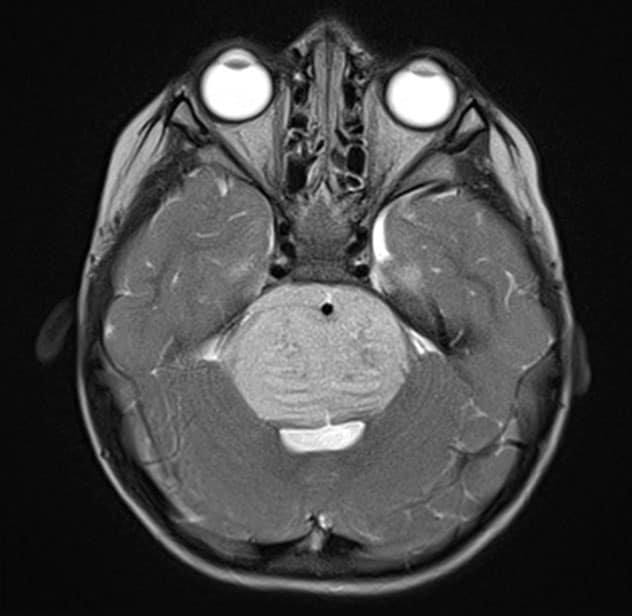

Sagittal T1-weighted MRI scan with contrast

Sagittal T1-weighted MRI scan shows the newly diagnosed diffuse midline glioma.